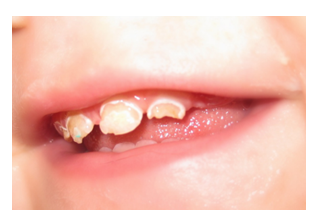

Karijes kod beba brzo napreduje i razara celu površinu zuba, pa ponekada može da podseća i na razvojne defekte.(Slika 5.)

Slika 5. Karijes kod beba brzo napreduje i podseća na razvojni defekt.